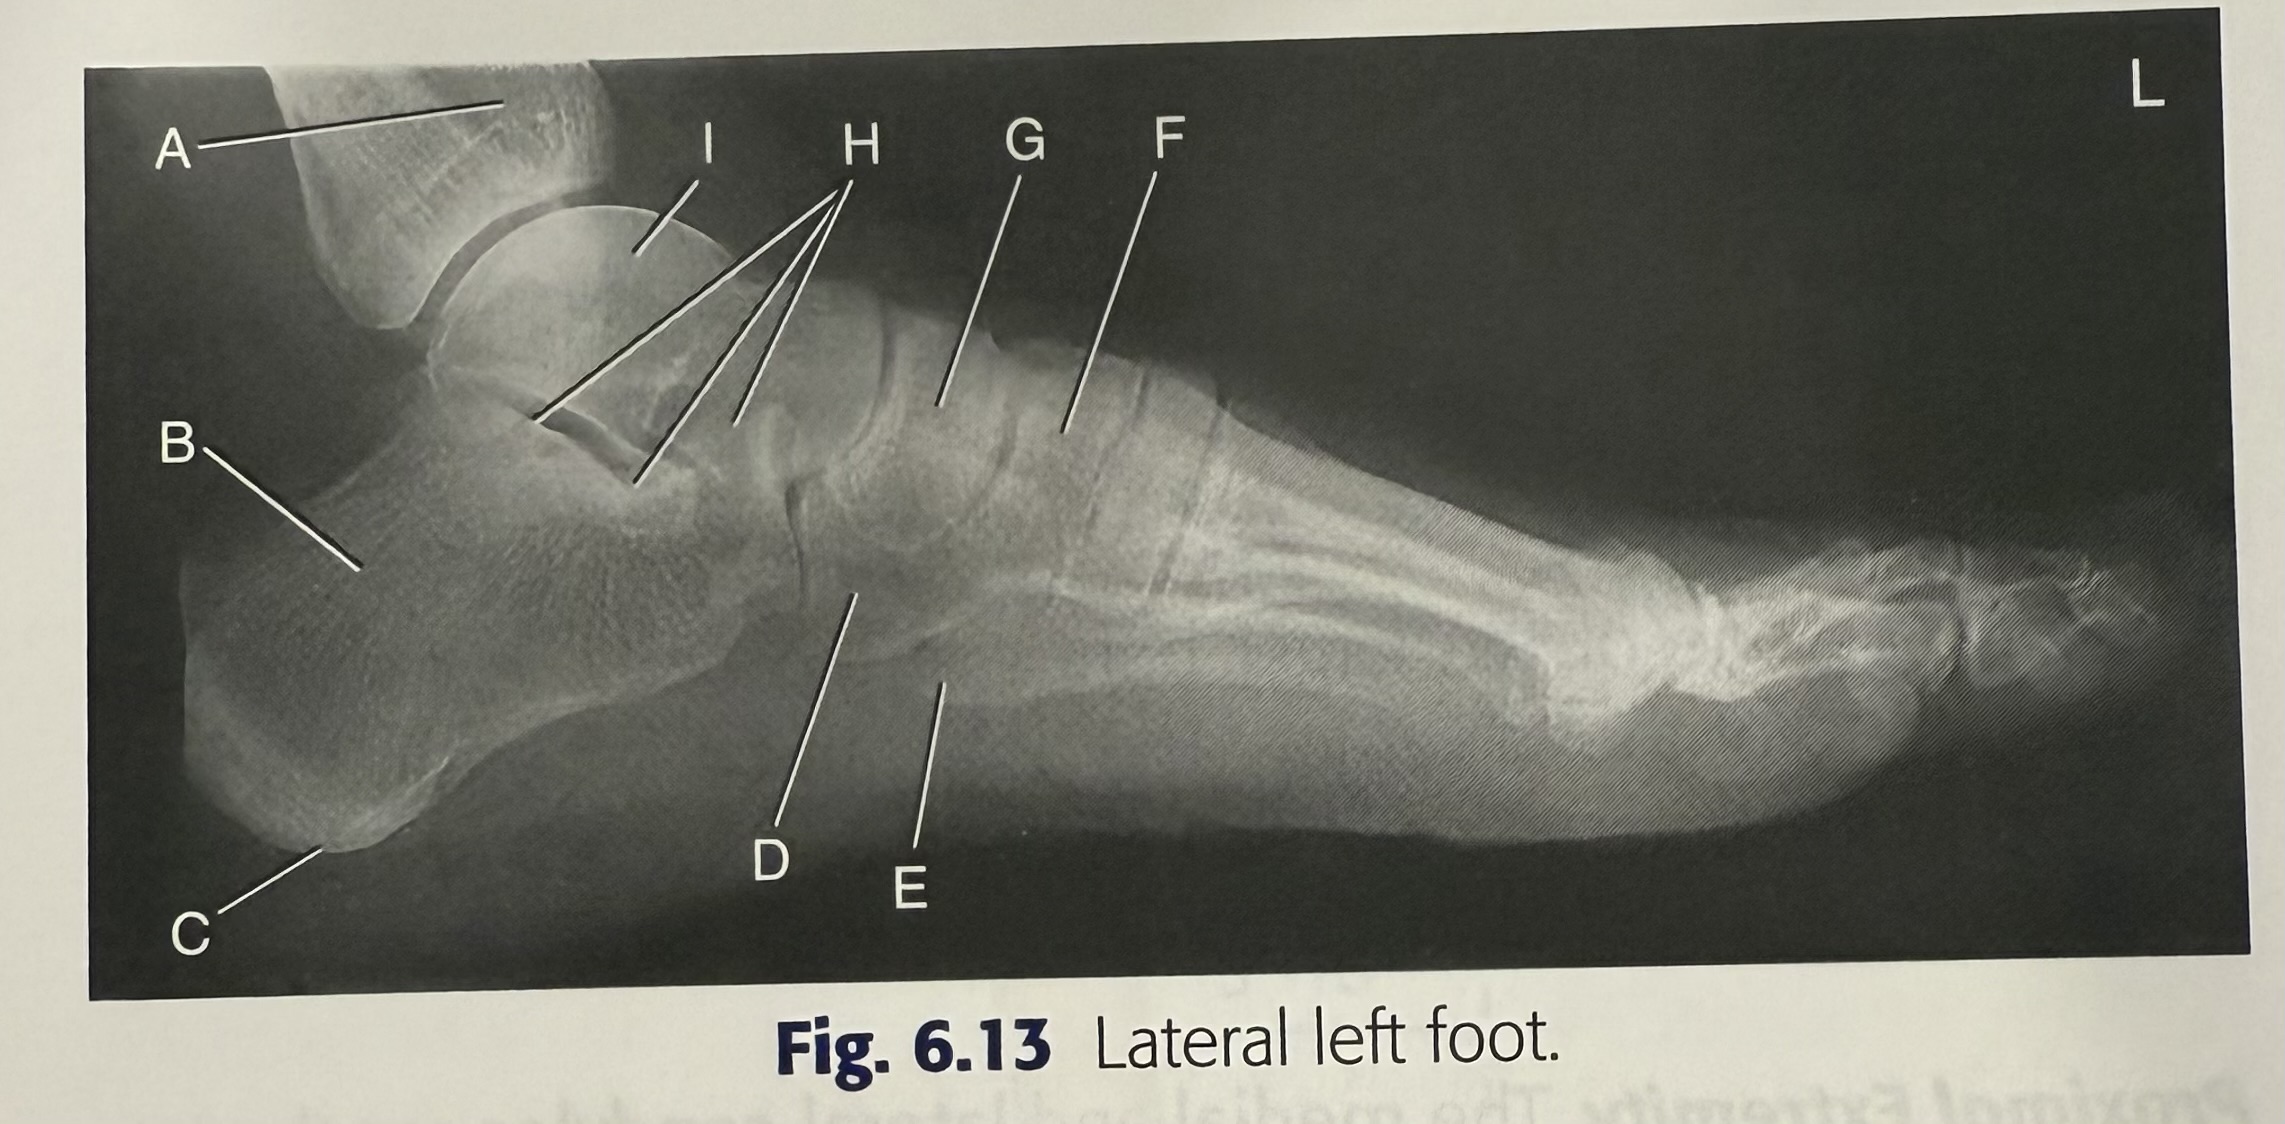

<p>H</p>

H

talus

14

New cards

<p>A</p>

A

cuboid

15